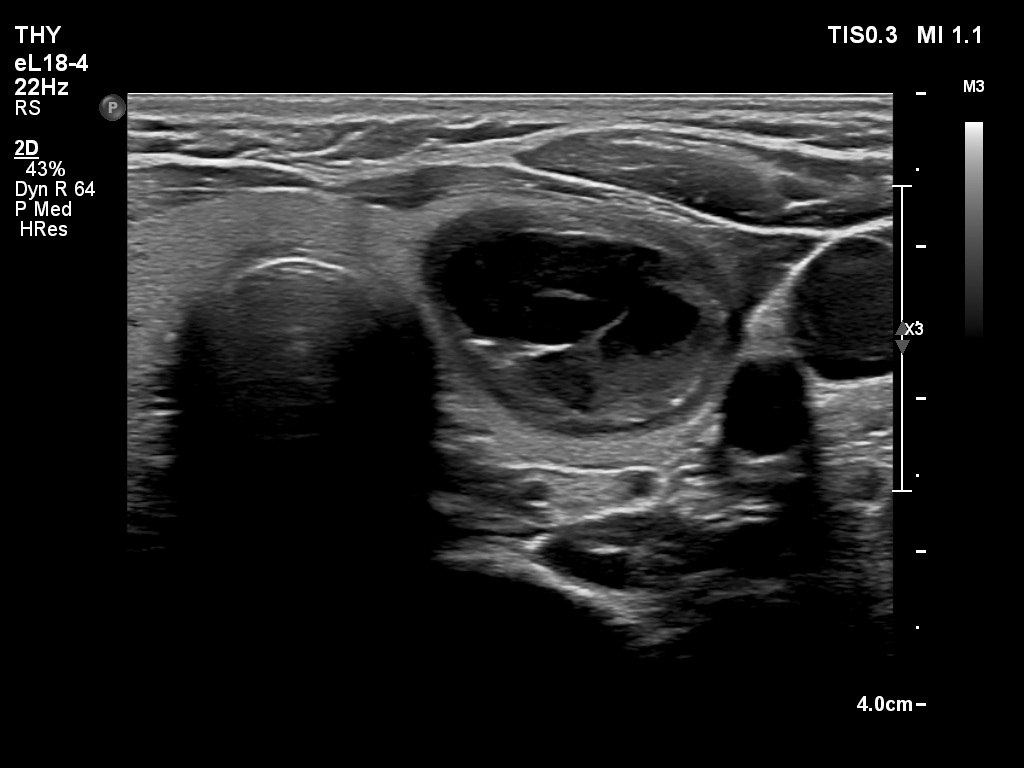

First examination (first and second rows of images)

Clinical presentation: A 39-yr old woman was referred for evaluation of a thyroid cyst which has refilled twice in the past. On the last aspiration, 2 years ago the maximal diameter of the nodule was 24 mm.

Palpation: no abnormality.

Laboratory test: 2.71 mIU/L.

Ultrasonography. The thyroid was echonormal. There was a central-type cystic nodule in the left lobe. The solid portion was echonormal-minimally hypoechoic. The lesion showed back wall cystic figures.Cytology was performed from the lesion in the left lobe and resulted in benign, cystic-colloid goiter.

Suggestion. Ultrasound in two years, in the event of complaints at once. If the cyst would recur ethanol sclerotherapy is advised.